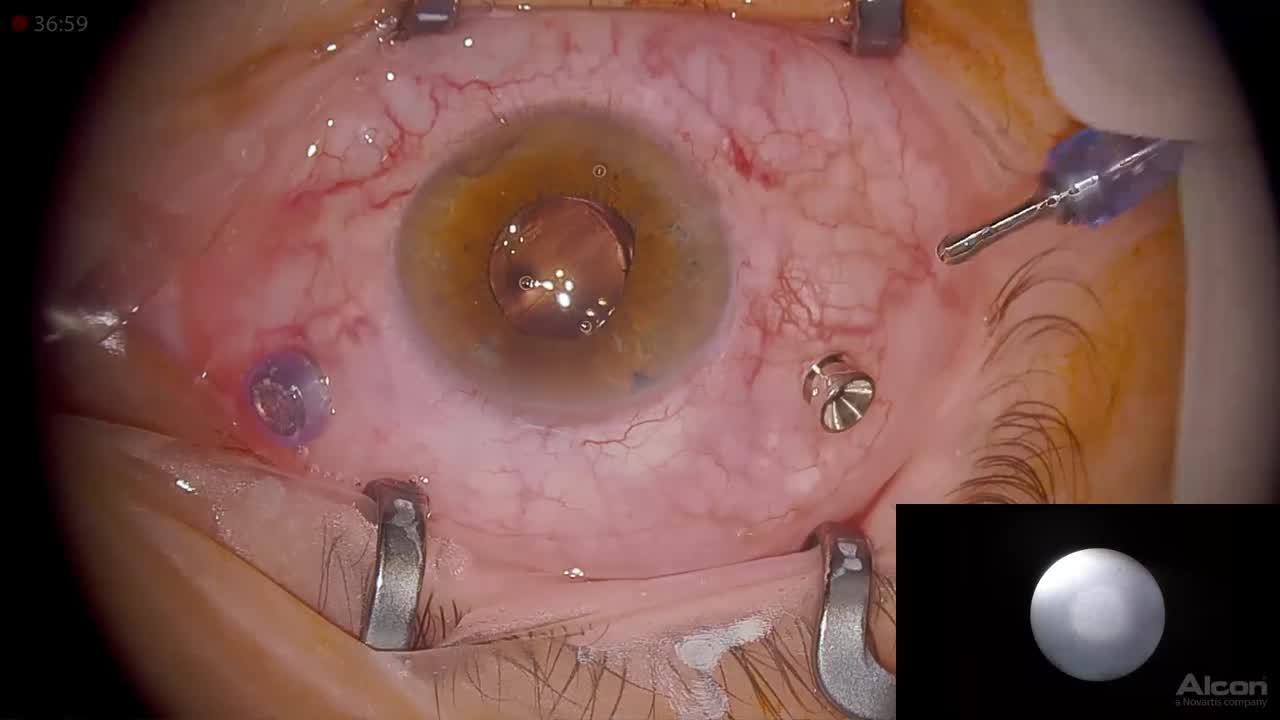

Myopic Macularschisis

Ehab El Rayes, MD